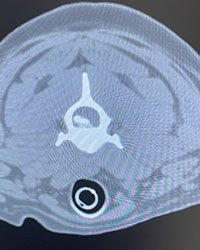

Stitchy was surrendered with no apparent health problems by an owner who had received her from a friend two weeks earlier for not getting along with an alpha femaile in the house.

Stitchy began cowering and yelping in pain. Following initial exrays and pain medication that she was not responsive to, she was referred by primary car to neurology. Imaging revealed a caldified stone in a neck vertibrae pressing against her spinal column, When removed using a ventral slot procedure by the surgion, she is expected to have a complete recovery with a 95% probability of success. We are told that after the procedure she will feel much better right away, compared to when she went in. Prognosis is excellent.